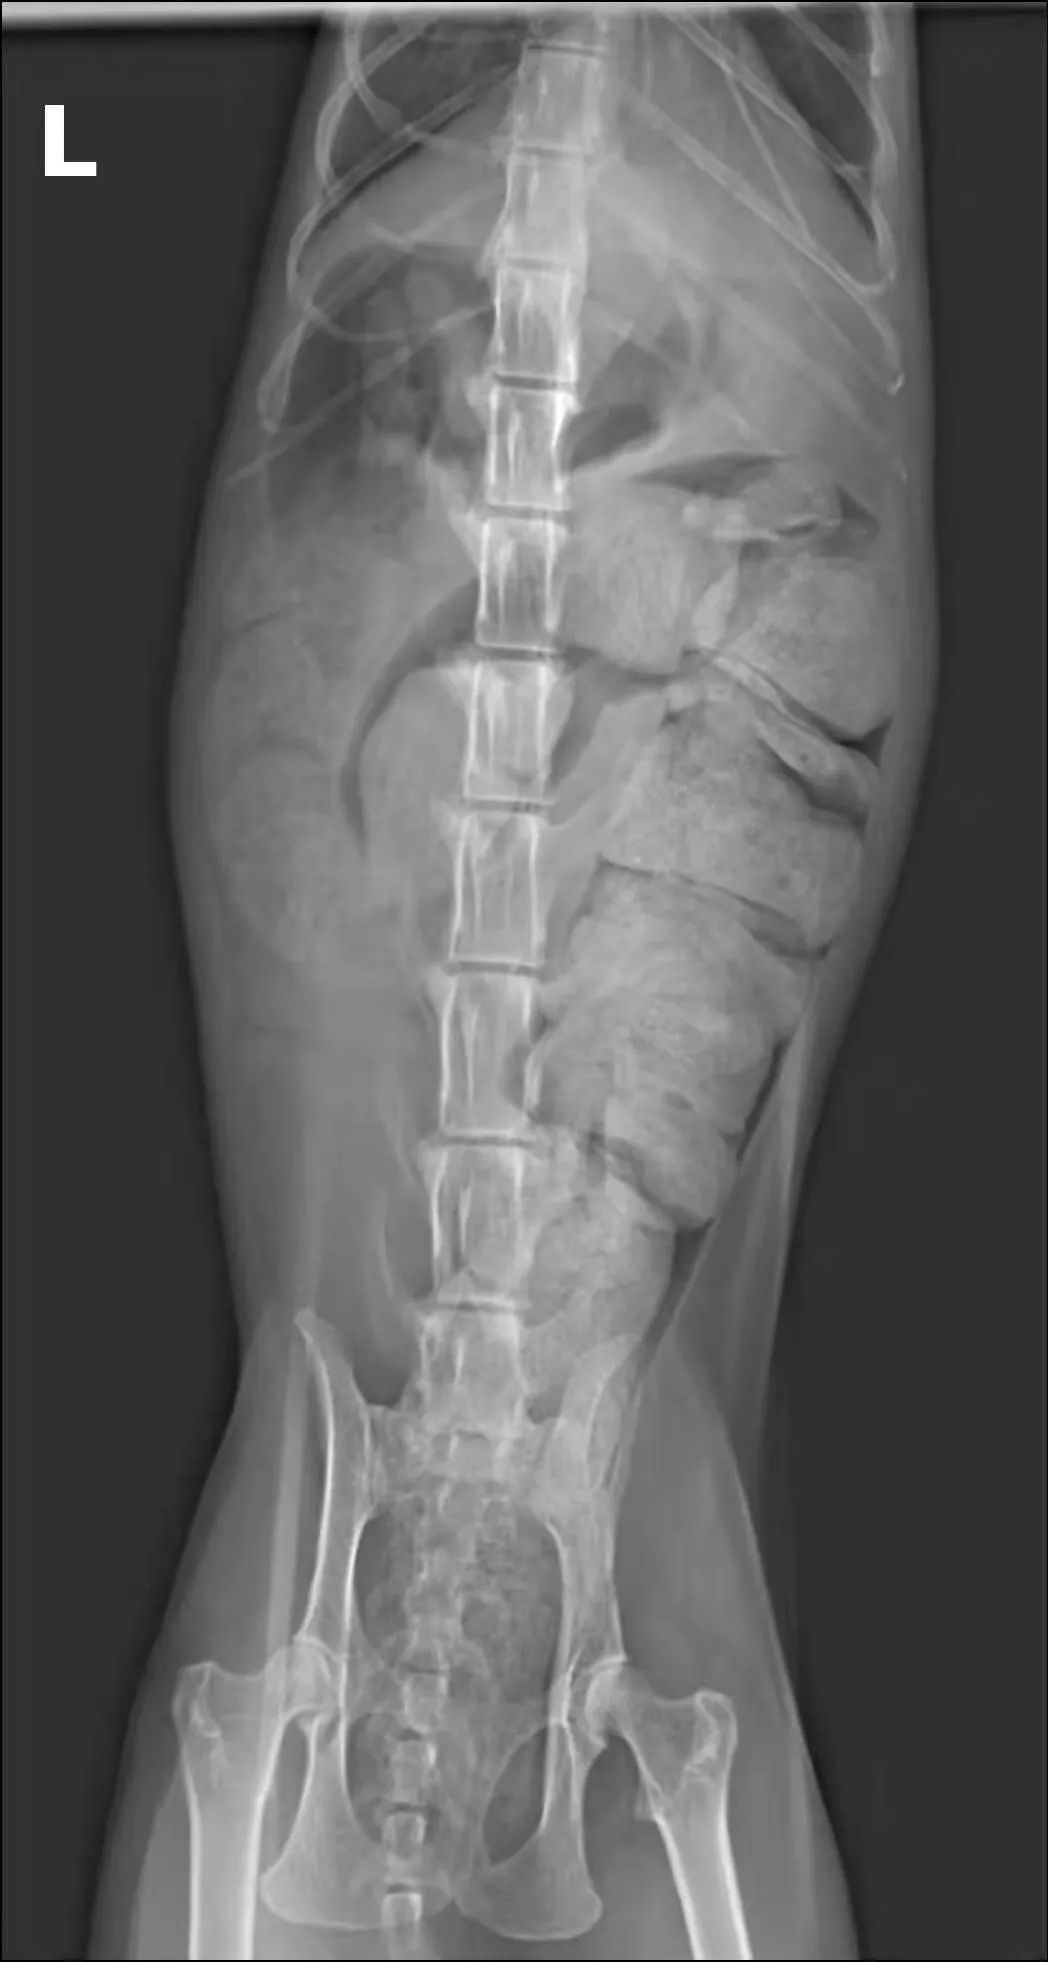

貓咪巨結腸 崇愛動物醫院

一例猫巨结肠症的诊疗 参考网